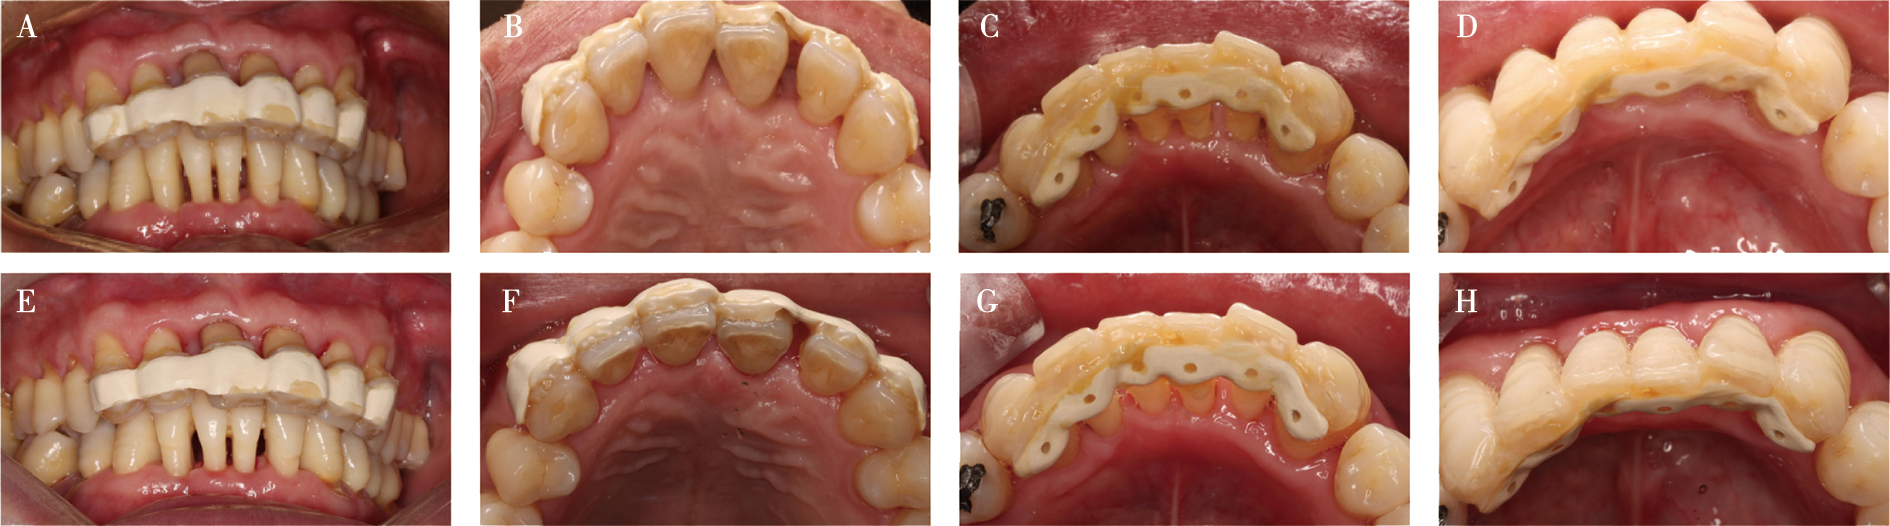

Zhang CR, Liu Q, Yang JW, et al. A digital technique for splinting periodontally compromised mobile teeth in the mandibular anterior region[J]. J Prosthet Dent, 2021, 125(4): 560-563.

Wang ZY, Guo LH, Deng K, et al. Additively manufactured zirconia periodontal splint integrated prosthesis: A proof-of-concept[J]. J Dent, 2025, 156: 105701.

Liu YC, Bai SZ, Zhong S, et al. Digital workflow for periodontal splinting with a guided device[J]. J Esthet Restor Dent, 2023, 35(4): 621-624.